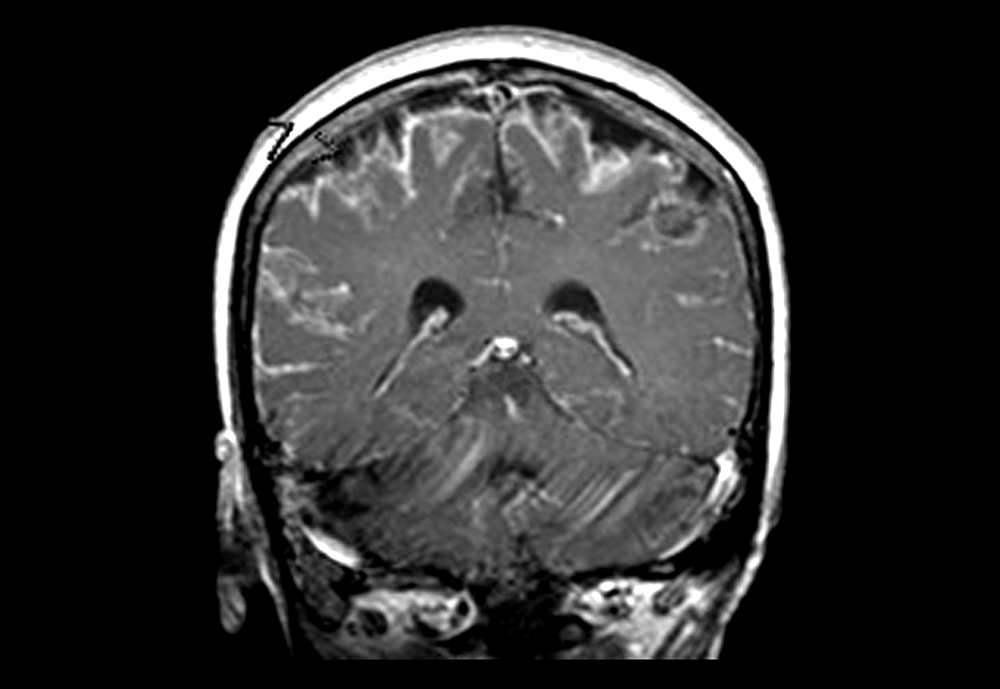

MRI of meningitis